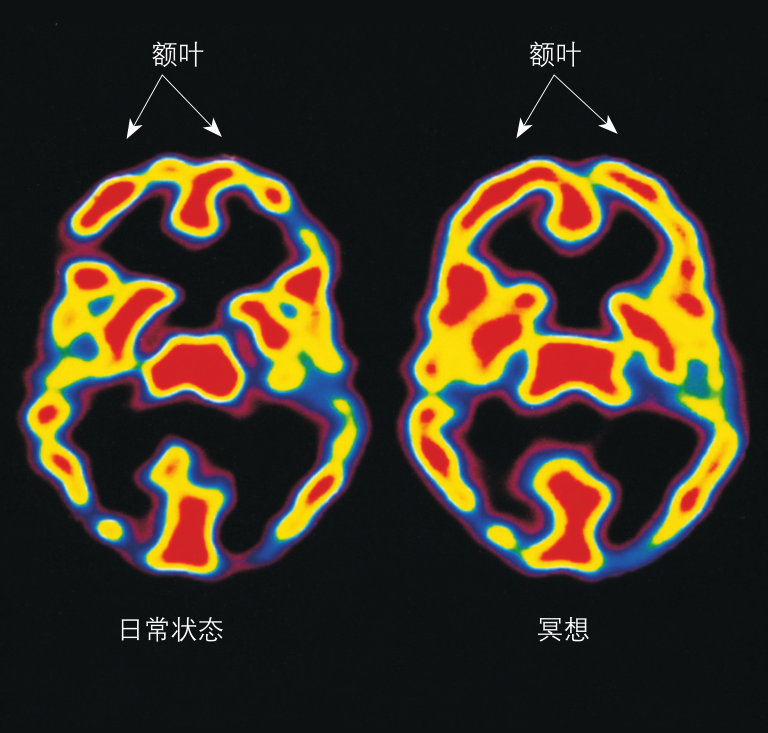

△冥想可以減少壓力和焦慮,此時大腦負責注意力的部分會更加活躍